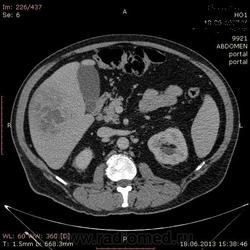

- https://radiomed.ru/sites/default/files/styles/case_slider_image/public/user/17529/img-0005-00001_3.jpg?itok=_YnH55Nh

На абсцесс похоже

На мой взгляд, абсцесс.

Тоже за абсцесс.

Cпасибо , коллеги.Сегодня больного прооперировали диагноз абсцесс правой доли печени.Оказывается больной когда - то получил тупую травму живота, об этом нам не говорил.....